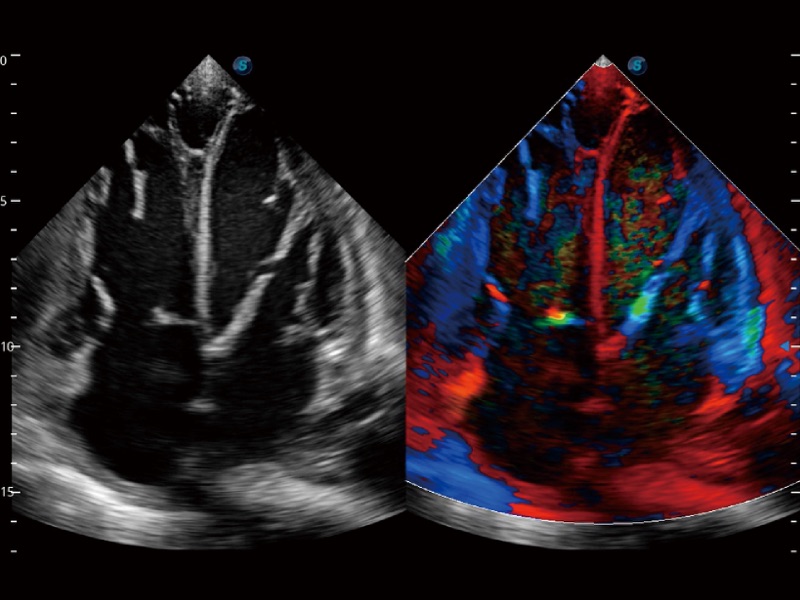

心血管应用

支持运动和药物负荷协议、多心动周期存储选择,为临床观察心肌负荷状态下的室壁节段运动、评估心肌缺血状态提供更多的解决方案。

通过心肌识别技术和二维斑点追踪技术相结合,计算心肌各节段的应变应变率、速度、位移并以曲线图显示,实现整体或者局部心肌定量分析。同时可呈现牛眼图直观和准确诊断心肌的运动情况。

高分辨率血流成像技术提高了对低速血流信号的检测能力。在提高空间分辨率的同时,也克服了血流外溢现象,为用户提供更加真实的血流动力学信息。